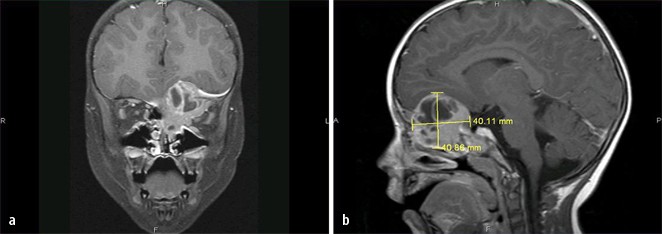

Figure 2 Aneurysmatische Knochenzyste Der Rhinobasis Bei Einem 3 Jahrigen Kind Springerlink

Figure 3 Aneurysmatische Knochenzyste Der Rhinobasis Bei Einem 3 Jahrigen Kind Springerlink